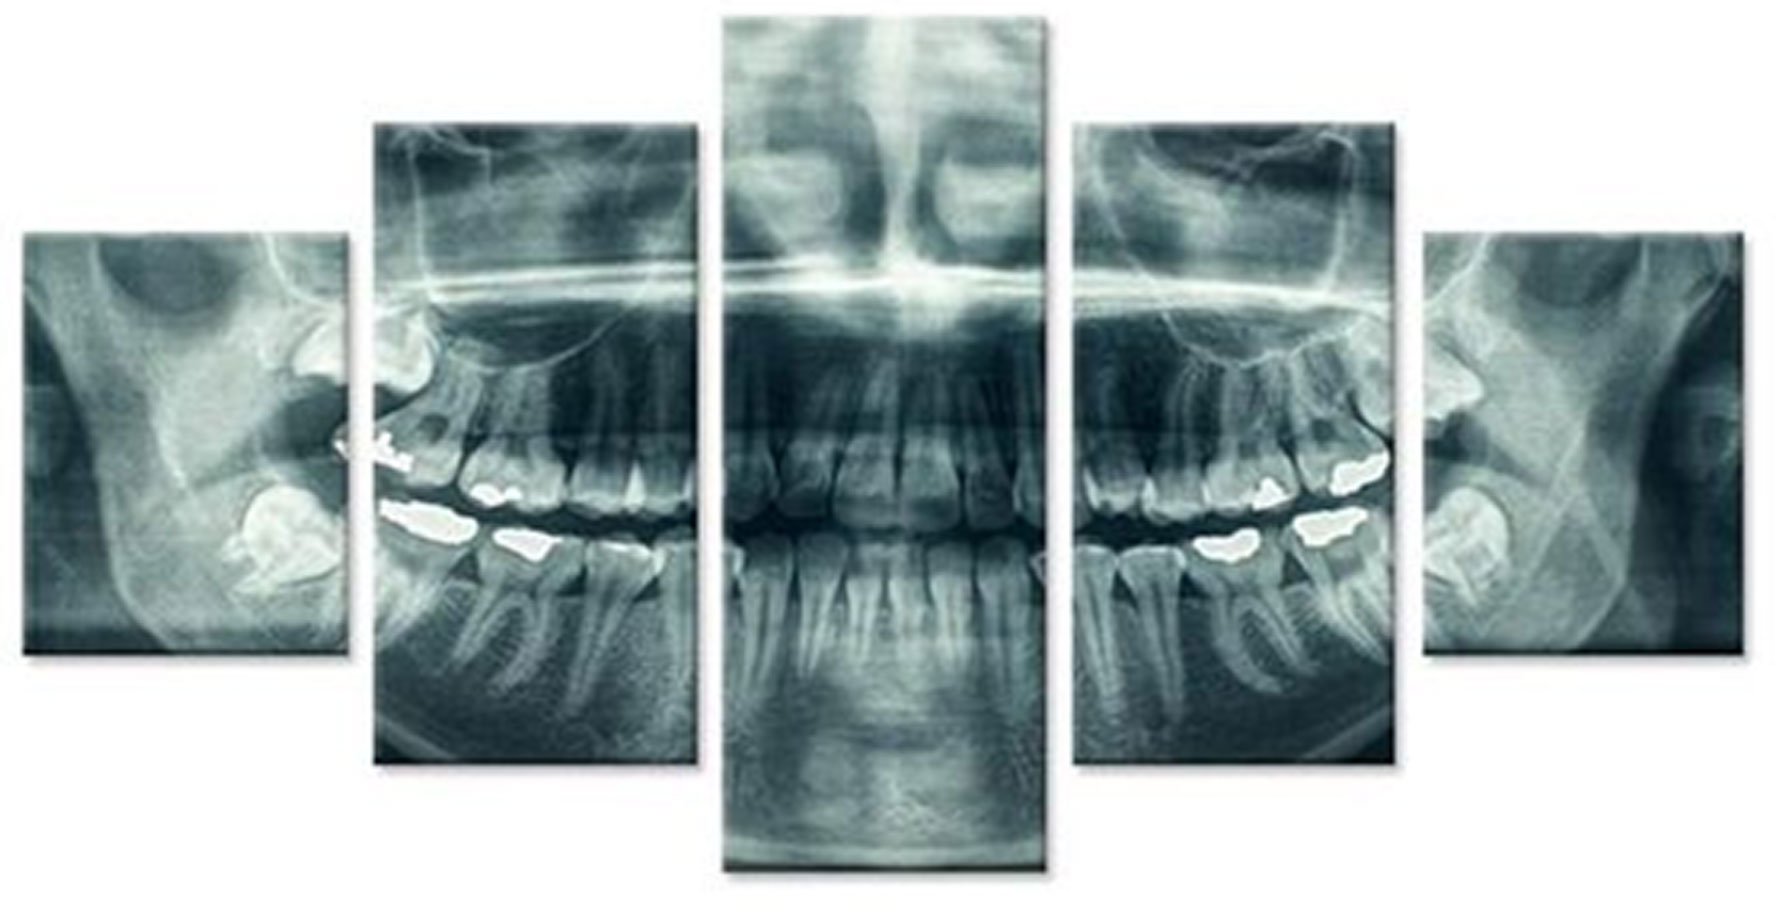

Преку нашите истражувачки активности, нашиот тим е запознаен со најновите научни наоди и може да ги исполни највисоките технолошки и професионални очекувања. За прегледи и проценки, имаме широк спектар на опции. Користиме различни методи за сликање, како што се проекциона радиографија, томографија и компјутерска томографија.

Kористиме најнова технологија за да овозможиме прецизен третман за нашите пациенти преку методи на снимање.